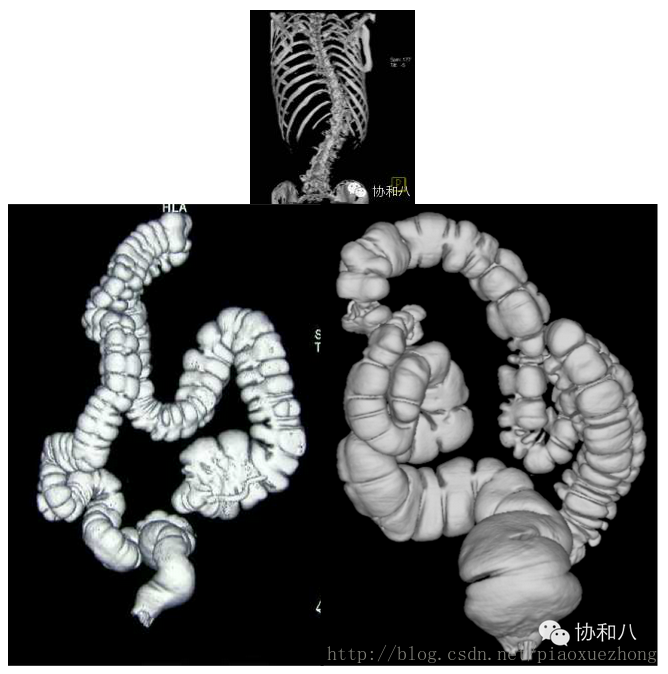

表面阴影遮盖(SSD)

表面阴影遮盖是将操作者的眼睛作为假设光源方向,投射到CT值在设定阈值以上的体素上则不再透过继续成像,仅呈现所有表面体素的集合立体图形,适用于显示CT值与其他结构相差较大的组织结构成像……(天地良心,我说的真是中文,如果觉得理解不了,继续看下文……)说得接地气些,SSD图像就像是黑白的塑形图像,所以临床上主要用于显示骨骼病变或是结肠CT重建: